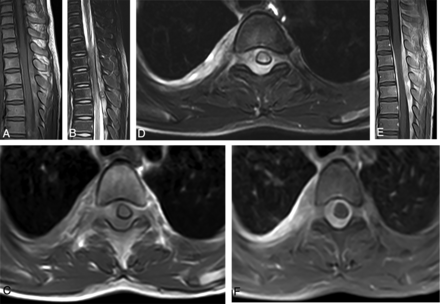

MR imaging of intraspinal paragonimiasis in a 12-year-old patient. Sagittal T1WI (A) and T2WI (B) show a fusiform-shaped mass located in the intraspinal extradural space at the junction of the thoracolumbar spine (T10–L2). The mass shows a heterogeneous signal with multiple patchy hemorrhage foci. Axial T1WI (C) and T2WI (D) show that the mass is located in the extradural space and connects with the irregular pleural lesions through the right intervertebral foramen. The spinal cord is compressed, but there is no edema. The sagittal view of the contrast imaging (E) shows a heterogeneous and significant enhancement in the extradural masses, and the axial view (F) also shows significant enhancement in the intervertebral foramen and pleural lesions. Meanwhile, the adjacent spinal meninges show thickening and enhancement.

The plain MR imaging scan of the 6 granulomatous lesions showed mixed signals with predominant isointensity on T1WI (Figs 1A, -C and 2A, -C) and hyperintensity on T2WI (Figs 1B, -D and 2B, -D), of which 5 fusiform-shaped lesions presented with multiple patchlike or irregular hemorrhagic foci with hyperintensity on T1WI within the masses (Figs 1A, -C and 2A, -C). The 5 patients undergoing the enhanced MR image showed heterogeneous and marked enhancement in the granulomatous masses (Figs 1E, -F and 2E, -F). The lesions in the intervertebral foramen and the pleura showed an enhancement pattern that was similar to that in the intraspinal lesions (Figs 1F and 2F). Furthermore, there was enhancement in the adjacent spinal meninges (Figs 1E and 2E).

In 5 of the 6 patients, the corresponding segment of the spinal cord exhibited various degrees of compression and edema, which was visible as hyperintensity on T2WI (Fig 1B, -D).